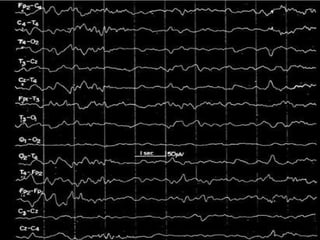

Hypnagogic Hypersynchrony

Fp1-A1

Fp2-A2

C3-A1

C4-A2

O1-A1

O2-A2

T5-A1

T6-A2

50 µV

1 sec

Roffwarg, Muzio, and Dement. Science, 1966